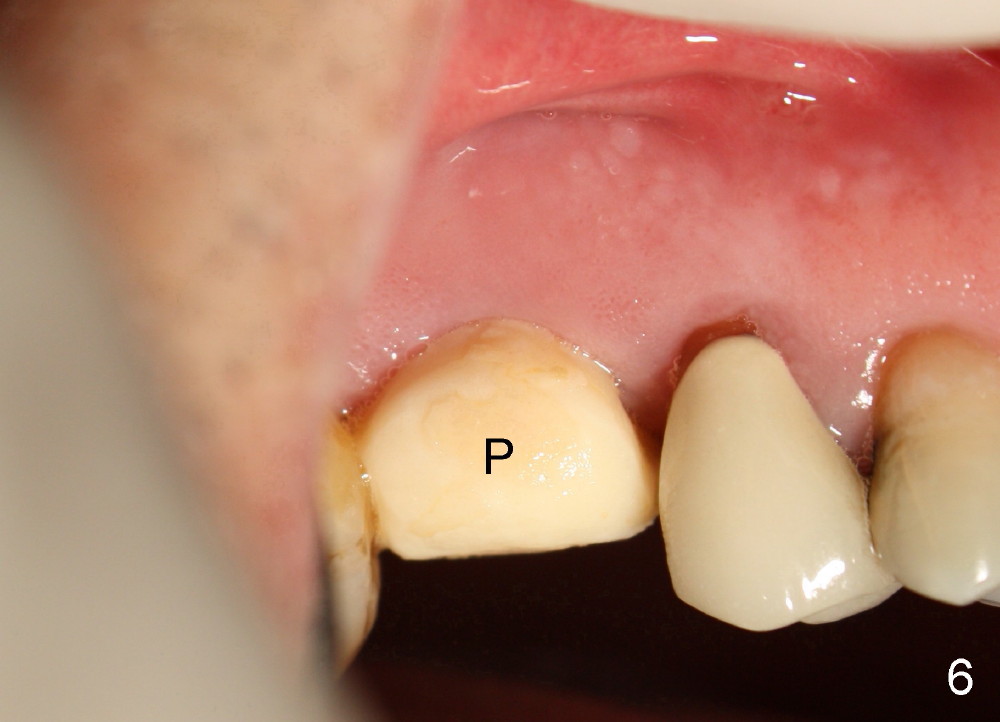

A 51-year-old man requests taking care of hemorrhage and odor associated with the tooth #3 (Fig.1). Due to religious and financial issues, the neighboring teeth will be treated later (supraeruption of #2 (arrow) and periapical radiolucency of #4 (*)). CBCT reveals that the septum of #3 is large enough to hold 4.5 mm implant (Fig.2). In fact osteotomy is created as planned in the septum using drills and taps (Fig.3 after removing 4.5x20 mm tap). Primary stability is obtained with a 4.5x20 mm implant (> 60 Ncm, Fig.4). The gap (*) is bone grafted; an abutment is placed (Fig.5 A); an immediate provisional is fabricated and cemented to cover the socket (Fig.6 P). When the socket heals in 3 weeks postop, the provisional and the abutment are removed for easy oral hygiene. Bone regenerates around the implant 3.5 months postop (Fig.7 *), but the 2nd molar has shifted mesially (arrow), presenting a restoration challenge.